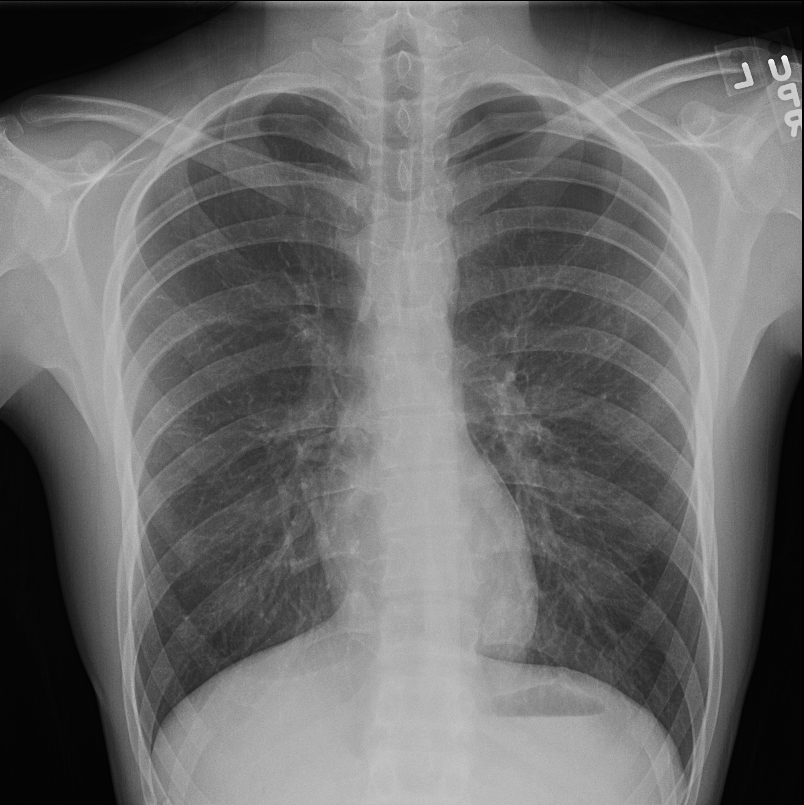

Рентген здоровых легких: примеры снимков и советы

Раздел: Сокровищница опыта